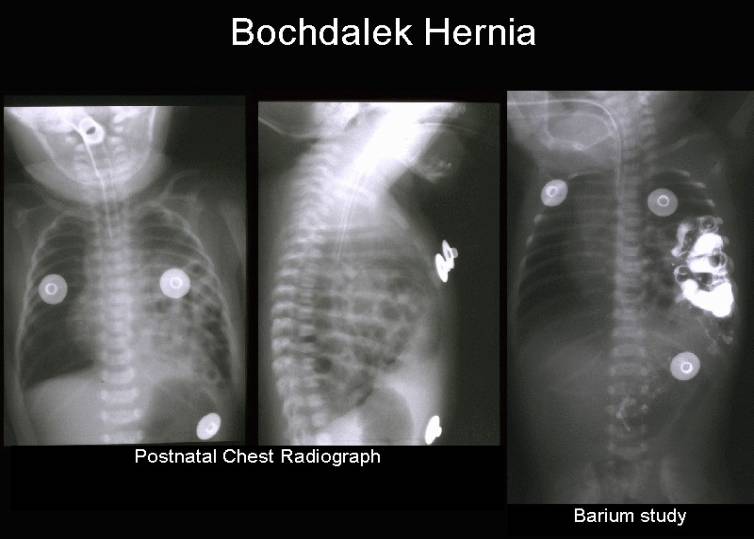

Анатомия диафрагмы и треугольника Бохдалека

Раздел: Визуальный дайджест